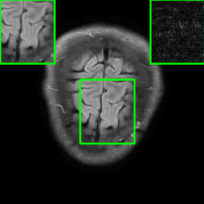

In Fig. 1-(a) and (b), we show reconstructed images using MoDL originating from a benign (i.e., undisturbed) input and a PGD scheme-perturbed input, respectively. It is evident that the worst-case input disturbance significantly deteriorates the quality of the reconstructed image. While one focus of this work is to enhance robustness against input perturbations, Fig.1-(c) and (d) highlight two additional potential sources of instability that the reconstructor (MoDL) can encounter during testing: variations in the measurement sampling rate (resulting in “perturbations” to the sparsity of the sampling mask in ) [20] and changes in the number of unrolling steps [22]. In scenarios where the sampling mask (Fig.1-(c)) or number of unrolling steps (Fig.1-(d)) deviate from the settings used during MoDL training, we observe a significant degradation in performance compared to the original setup (Fig.1-(a)), even in the absence of additive measurement perturbations. In Section IV, we demonstrate how our method improves the reconstruction robustness in the presence of different types of perturbations, including those in Fig.1.

Table I presents PSNR and SSIM values for different smoothing architectures with different training schemes, along with vanilla MoDL as a baseline using the brain dataset. The evaluation is conducted on the clean, noisy (with added Gaussian noise), and worst-case perturbed (using PGD for each method) measurements. As indicated by the PSNR and SSIM values, we observe that our method, SMUG, outperforms RS-E2E and vanilla MoDL in robust accuracy, i.e., image quality with perturbations. This observation is consistent with the visualization of reconstructed images for the brain dataset in Fig. 5. Furthermore, we observe that Weighted SMUG outperforms SMUG in robustness. However, weighted SMUG requires longer time for training, which represents a trade-off. The clean accuracies of Weighted SMUG and SMUG are similar to vanilla MoDL indicating a good clean accuracy vs. robustness trade-off.